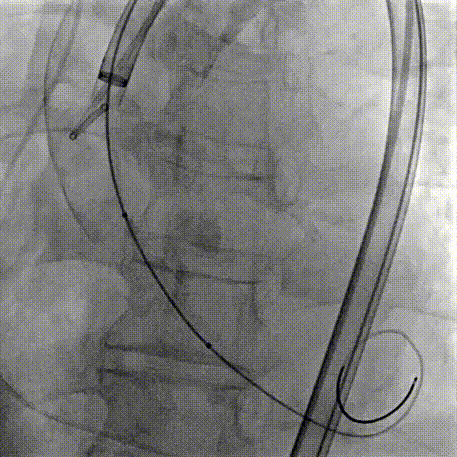

Step 2.建立大鞘通路:大鞘通过升主、边进入边加弯,避免剐蹭弓部斑块

Step 4.输送系统进入:过弓性能优异,悬空通过,整体过程未将鞘管顶起至弓顶部

过弓示意图

手术中其实有个关键点,在可调弯鞘过弓的时候,我们特意放慢了速度,一遍进一遍调弯,确保每一步都不触碰弓顶钙化。这台手术的成功,本质上是 “病变特点和器械特性” 的精准匹配。对同类型来说,碰到瓷化升主动脉合并复杂弓的病例,建议术前一定要把钙化范围、弓部角度这些解剖细节分析透,器械选择上不用局限于单一方案,多考虑协同作用,或许能找到更安全的路径。毕竟对我们来说,每台复杂手术的目标都一样:在保证安全的前提下,给患者带来最好的长期获益。